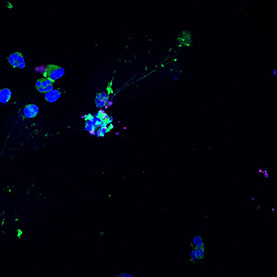

Pathogens are a major factor affecting the evolution of primates. We know very little about how historical pandemics have affected the genomes of different populations. This image results from research that examines how genetic variation and historical exposure to one of the most virulent pathogens known in human history, the plague, has affected immune system evolution and human health.

In the center of this image we see human white blood cells (labeled blue) confronted with bacteria. To protect the body from this invader, the cells capture the bacteria by throwing nets made from their own DNA. The cells are laid over tracks that evoke those seen in bubble chambers, another innovation used by researchers to see into the smallest spaces and understand movement and action on the smallest scales.

Scientist Collaborators

Jessica Brinkworth Laboratory

Zeiss LSM 700 Confocal Microscope

National Science Foundation